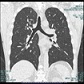

最新の技術により以前より低被ばくで全身の横断面像が撮影でき、再構成することにより冠状断面像、矢状断面像も観察できます。

胸部横断面像 胸部冠状断面像 胸部肋骨立体像